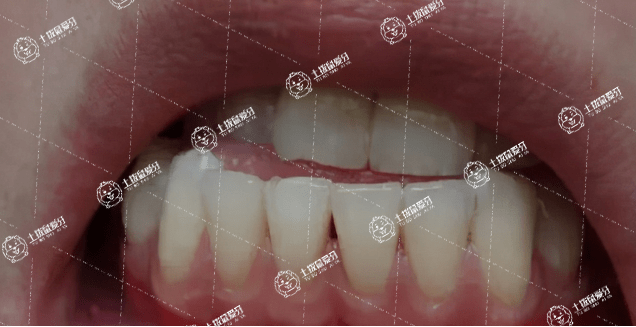

地包牙在牙齒疾病當(dāng)中也可以說(shuō)是一種極其常見且比較熟悉的一種牙齒畸形,而且地包天在兒童牙齒不整齊的現(xiàn)象還是比較多的,當(dāng)牙友們?cè)诔霈F(xiàn)地包天的話,往往還是會(huì)因?yàn)槠綍r(shí)自身不良習(xí)慣,或是、頜骨受傷或遺傳因素造成的。地包天牙齒矯正方法適合多大年齡?這或許是牙友們比較關(guān)注的事情,對(duì)此,接下來(lái),我們一起來(lái)了解一下。

地包天臨床上是指反頜,是指下前牙咬在上前牙的外面,可以通過(guò)地包天矯正術(shù)或者佩戴牙套進(jìn)行改善,手術(shù)主要是通過(guò)截骨并前移后縮的骨組織。佩戴牙套主要是結(jié)合牙齒生長(zhǎng)的方向,設(shè)計(jì)矯正方法。